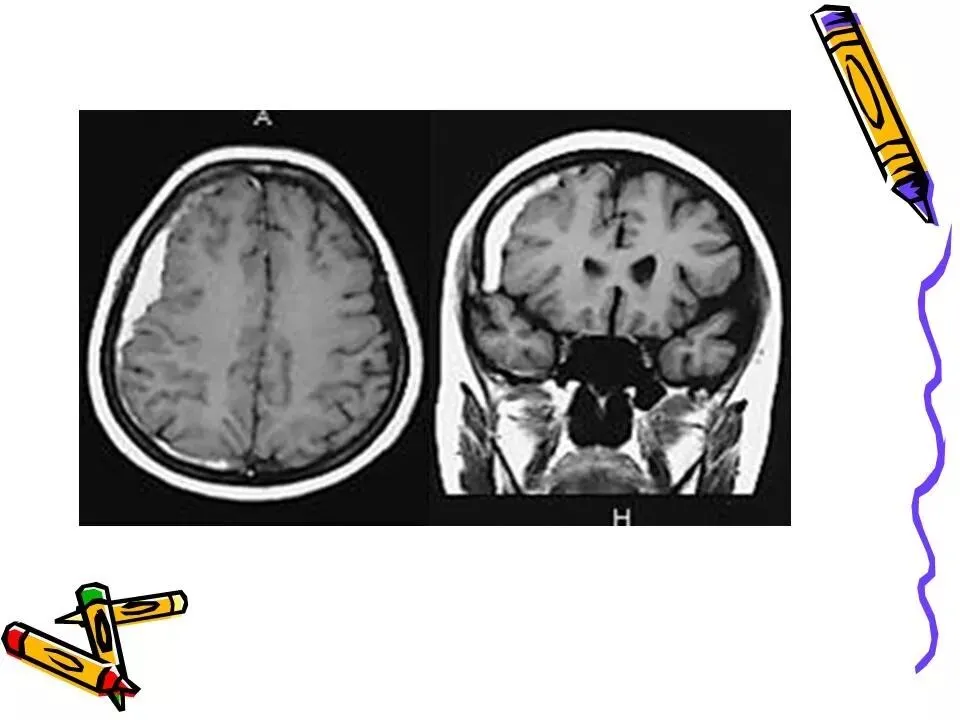

>常见颅脑外伤CT诊断(PPT)

常见颅脑外伤CT诊断(PPT)